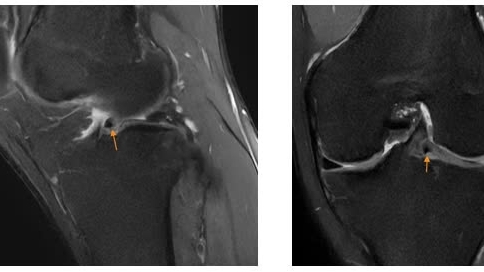

![]() |

| Tiêm phòng cúm cho trẻ là biện pháp phòng bệnh tốt nhất |

PGS.TS.BS Tạ Anh Tuấn - Trưởng khoa Điều trị tích cực Nội khoa, Bệnh viện Nhi Trung ương đưa ra những lưu ý, khuyến cáo mà cha mẹ cần biết về bệnh, giúp cha mẹ có thể ứng phó và chăm sóc đúng cách cho trẻ mắc cúm B.

PGS.TS.BS Tạ Anh Tuấn - Trưởng khoa Điều trị tích cực Nội khoa Bệnh viện Nhi Trung ương cho biết, tiêm phòng cúm (vắc xin cúm bao gồm cả cúm A và B, được chỉ định cho trẻ từ 6 tháng tuổi) là cách tốt nhất để giảm nguy cơ mắc bệnh cúm. Tiêm phòng hàng năm sẽ tăng cường khả năng miễn dịch cho trẻ chống lại các chủng cúm gần đây nhất, giúp phòng các biến chứng nặng nếu nhiễm bệnh.